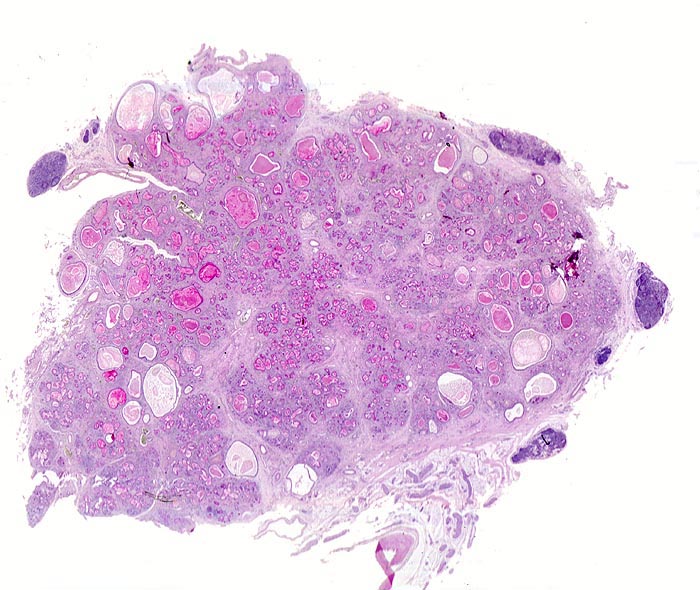

Morphologische Merkmale:

• Atrophie und ausgeprägte Fibrose des exokrinen Pankreas (Azini).

• Erhaltenes endokrines Pankreas (Inseln).

• Zystisch dilatierte Pankreasgänge gefüllt mit Schleim.

• Geringes gemischtes Entzündungsinfiltrat in den Fibrosearealen.